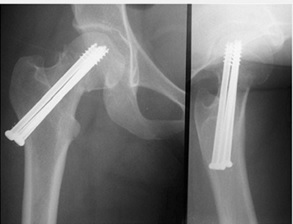

شكستگي گردن فمور همراه با شكستگي شفت در همان طرف

معمولاً اين نوع شكستگي در تصادفات رخ ميدهد. در جريان تصادفات ، زانو و ديستال ران به شدت با داشبورد اتومبيل برخورد كرده و علاوه بر شكستگي شفت فمور ، تمام نيرو در ناحيه شكستگي خنثي نشده و مقداري به گردن فمور انتقال مييابد و باعث شكستگي در اين ناحيه ميشود. در 50% موارد اين شكستگيها در بدو امر تشخيص داده نميشود. حتي اگر در بدو امر شكستگي گردن فمور همراه با شفت مشاهده نشده باشد در انتهاي عمل جراحي فيكساسيون شفت فمور ، راديوگرافي هيپ بايستي مجدداً تكرار شود.

در 6-5% شكستگيهاي شفت فمور ، شكستگي گردن فمور نيز به همراه آن رخ داده است. شكستگي شفت فمور معمولاً در ناحيه وسط استخوان و چند قطعه است. در اين موارد درمان عبارتست از عمل جراحي و ثابت كردن هر دو شكستگي.

شكستگي گردن فمور همراه با شفت فمور . شكستگي گردن فمور با سه عدد پيچ و شكستگي شفت فمور با نيل رتروگراد فيكس شده است.